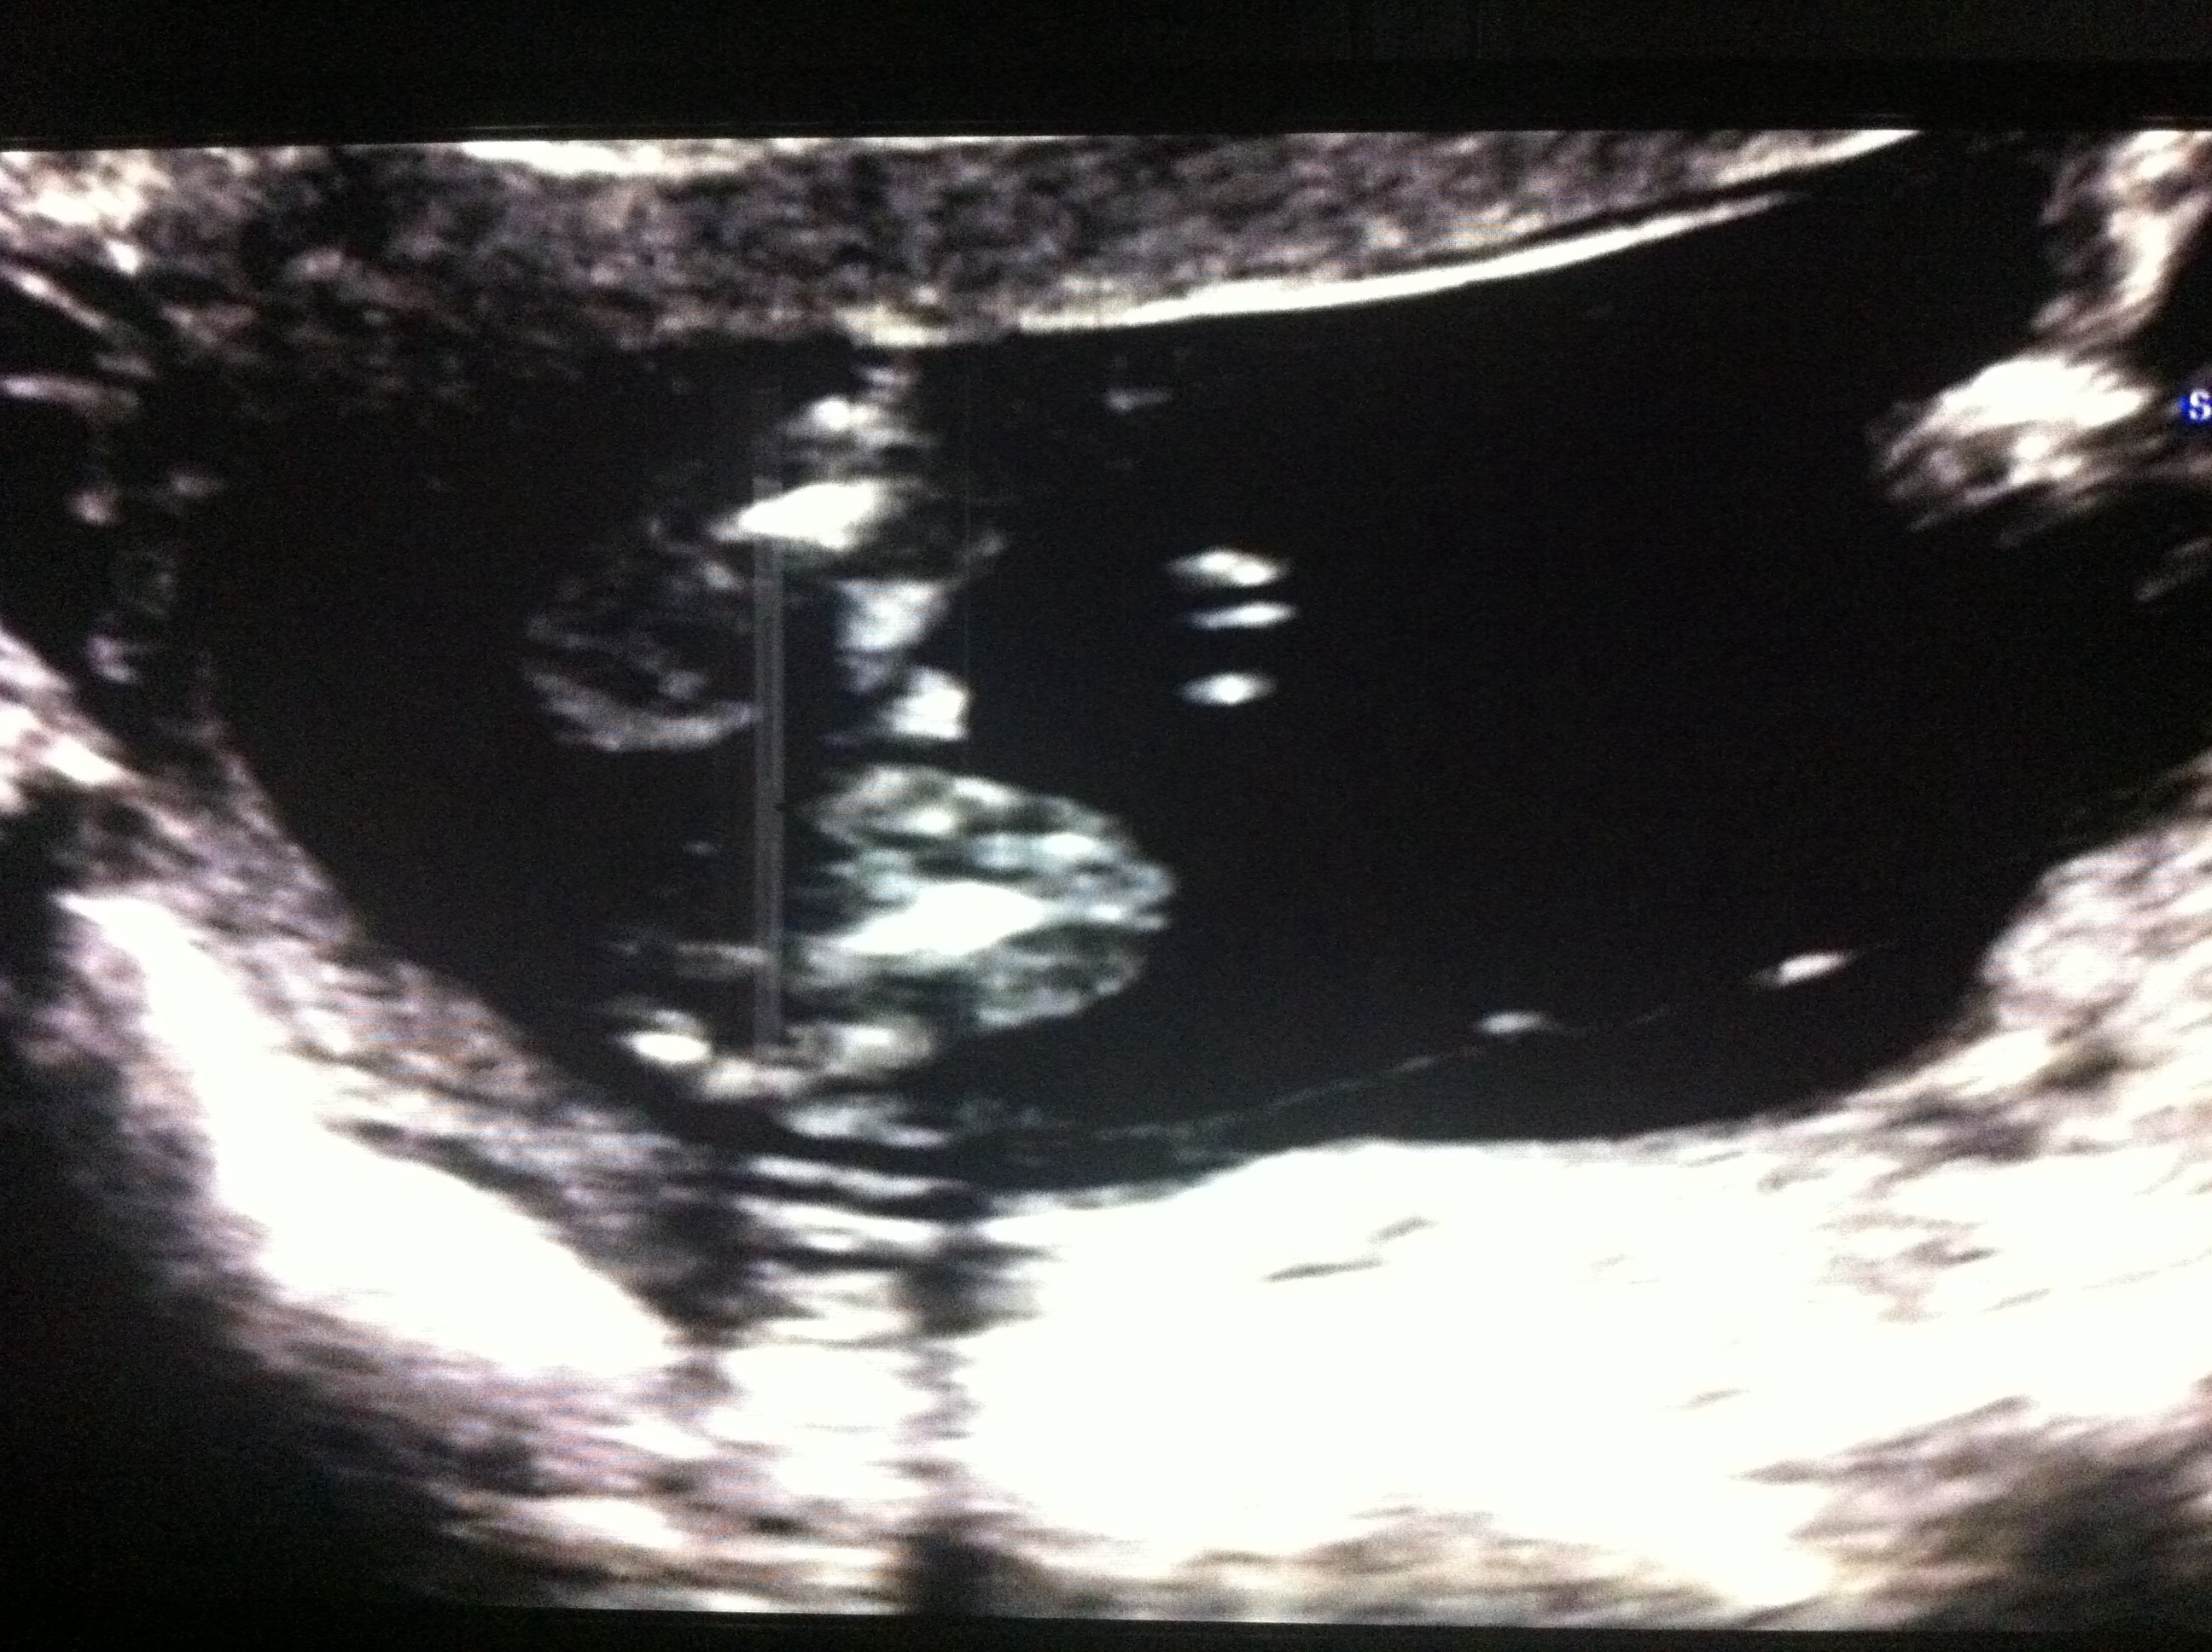

These are at 16 weeks the tech was sure 100% girl , I posted them on in gender and most people saying boy one woman in particular being very insensitive telling me to go get a refund and congratulations on my son outlining a penis on my picture. I already have 2 boys and this is my last I really was over the moon I was getting a girl now I'm so confused my 20 week scan at the hospital isn't till 11th July I don't think I can wait that long x here's the pics thank you xAttachment 19329Attachment 19330